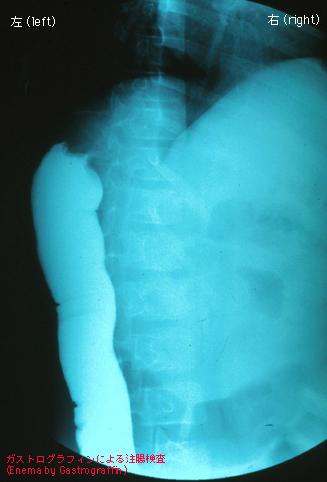

Criteria of Hist.ClassificationMalignant epithelial tumor/Adenocarcinoma

LocationLarge intestine(Colon)/Transverse colon

Technique, MethodX-ray

Macroscopic TypesType 2 Ulcerated type with clear margin/

Size30 - 34

Depth of Tumor Invasionsubserosa (subadventitia)